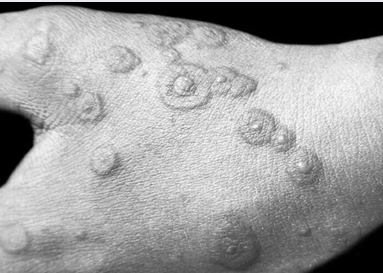

Рис. 1.1. Местная токсико-аллергическая реакция

Многоформная экссудативная эритема (МЭЭ) – острое, редко рецидивирующее заболевание кожи и слизистых оболочек, возникающее от разных причин и отличающееся характерным сочетанием многих первичных элементов сыпи (пятна, папулы, волдыри, пузырьки, пузыри). Может быть вызвана как инфекцией, так и лекарственными препаратами. Наиболее часто индукторы МЭЭ – это сульфаниламиды, производные пиразолонового ряда, тетрациклины, барбитураты, аспирин, диуретики, прогестерон, стрептомицин и др. Первичным элементом является пятно эритемы, которое в течении двух суток увеличивается до 1-2 см в диаметре, превращается в папулу. Сформированный элемент имеет резкие границы, более темные цианотичные края и центр с более светлой розовой полоской между ними, что придает вид бычьего глаза, ириса, или мишени (рис. 1.2). В центре пятна может располагаться папула или пузырек. Наиболее частая локализация – тыльная и ладонная поверхность кистей и подошвенная стоп, разгибательные поверхности предплечий и голеней, наружные гениталии. Сыпь располагается симметрично. При распространенной МЭЭ поражается практически все участки кожи, за исключением волосистой части головы.

Рис.1.2. Округлые отечные розовые пятна в центре, которого расположен пузырек ("бычьей глаз") при МЭЭ